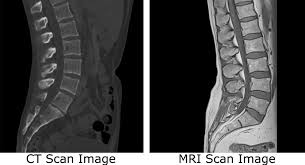

CT촬영 MRI촬영

CT검사는 인체에 X선을 투과, 횡단면상 단층으로 영상을 획득해 진단에 이용한다고 한다. 주로 뼈 등 단단한 조직 내부 확인을 위해 사용되며, 우리 몸 대부분 장기는 CT로 확인할 수 있다고 한다.

반면 자기공명영상인 MRI는 강한 자석과 전자기파를 통해 촬영하는데 강한 자기장이 발생하는 통 안에서 인체에 해가 없는 고주파를 투여, 공명되는 전자파를 측정한 영상으로 질병을 진단한다고 한다. 또한 MRI는 종·횡단면을 모두 확인할 수 있다는 장점이 있다고 한다.

X-ray 검사에서 이상 소견이 보였을 때 추가로 진행하는 CT 검사는 10~15분 정도로 1시간 이상 시간이 소요되는 MRI에 비해 검사 시간이 짧다. 또한 밀폐된 공간에서 하는 검사가 아니기 때문에 폐쇄공포증 환자도 무리 없이 검사를 받을 수 있고 뼈 질환과 척추관 협착증은 오히려 MRI 보다 선명한 결과를 확인할 수 있어 뼈의 골절 유무 확인은 주로 CT 검사를 시행한다고 한다.

그러나 MRI는 CT에 비해 출혈, 골절 등의 병변이 잘 보이지 않는 경향이 있어 응급상황에서는 최초 검사로 CT를 우선 시행하는 경우가 많고 세밀한 판독을 위한 추가 정밀검사 방법으로 MRI를 시행하게 된다고 한다. 한편 MRI는 근육파열, 신경손상 등을 확인하는데 효과적이고 특히 디스크 판독에도 탁월하다고 한다.